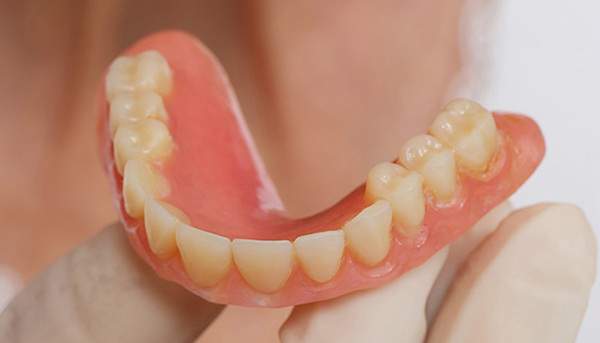

ですのでいざ出来上がってみると見た目が変だったり、噛み合わせがおかしいといったことがでてきやすいのです。 また、左の写真は総入れ歯で自費の入れ歯ですが、このように金属を使うことで入れ歯の厚みを薄くすることができます。

薄くすると、違和感が少ないのと、金属を使うことで、食べ物のの温度を上顎に伝えられるというメリットがあります。 その他、マグネット(磁石)やインプラントを使った入れ歯ですと、パカパカ外れにくいといったことを解消できます。

金属を使用して、薄く違和感が少ない入れ歯が完成しました。 また、見た目にも気を使い、バネが見えにくい様な構造にしました。

義歯は下顎で、しっかり噛めること、違和感の少ないものという希望があったため、なるべく入れ歯を薄く作成するために金属をしようした義歯とした。

入れ歯は極力薄くするために金属を使用しました。しっかり噛める様にするため、ノンメタルクラスプデンチャーにはしませんでした。